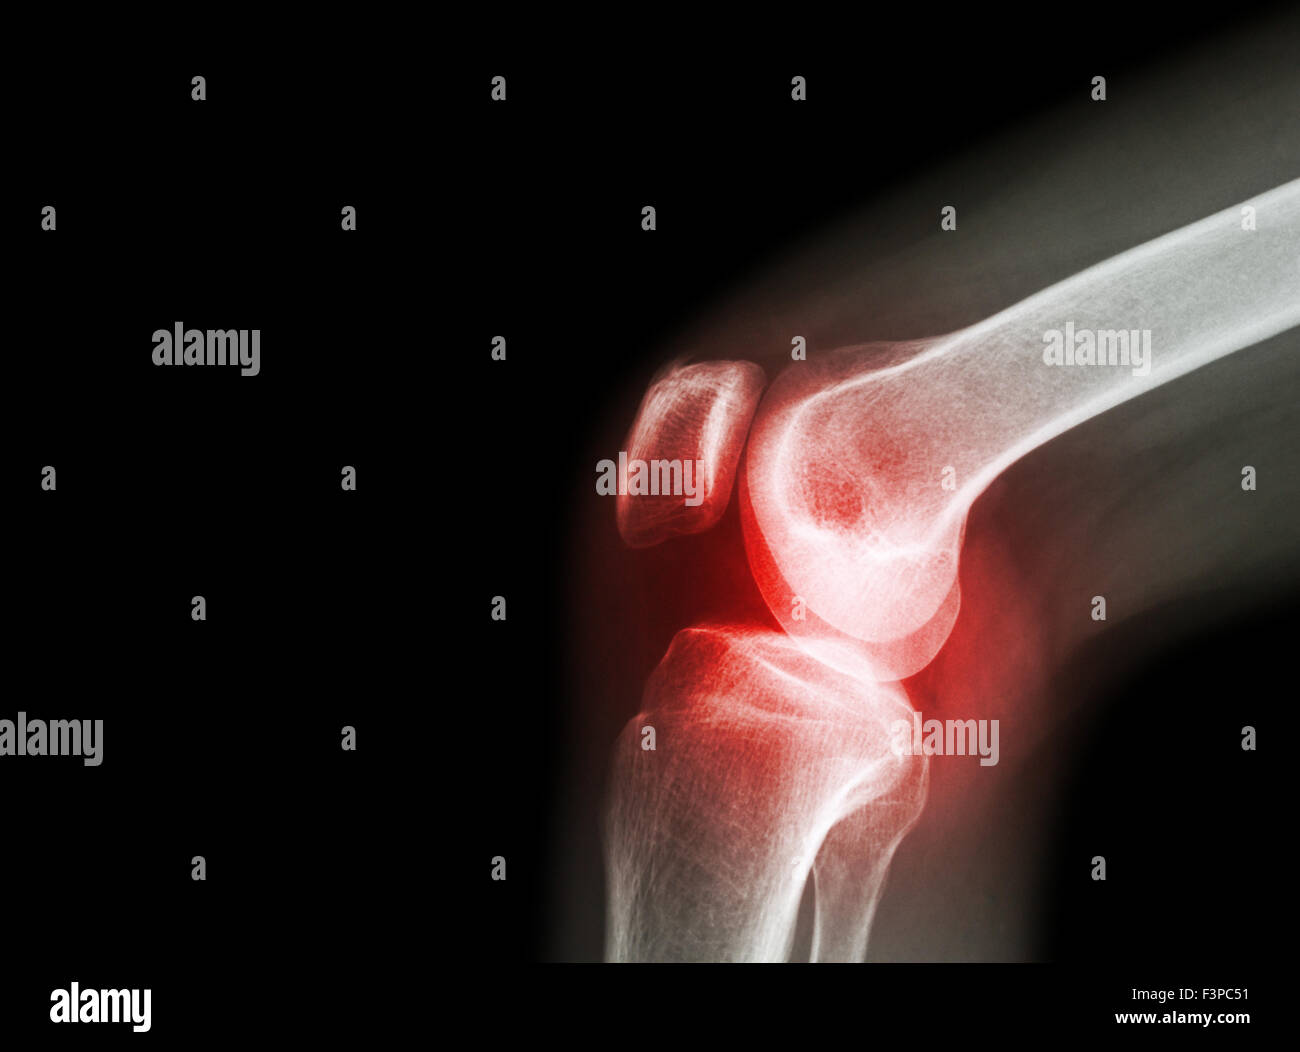

Film x-ray articulation du genou avec l'arthrite ( la goutte, l'arthrite rhumatoïde, l'arthrite septique , l'arthrose du genou ) et la zone vide sous Banque D'Imageshttps://www.alamyimages.fr/image-license-details/?v=1https://www.alamyimages.fr/photo-image-film-x-ray-articulation-du-genou-avec-l-arthrite-la-goutte-l-arthrite-rhumatoide-l-arthrite-septique-l-arthrose-du-genou-et-la-zone-vide-sous-88388299.html

Film x-ray articulation du genou avec l'arthrite ( la goutte, l'arthrite rhumatoïde, l'arthrite septique , l'arthrose du genou ) et la zone vide sous Banque D'Imageshttps://www.alamyimages.fr/image-license-details/?v=1https://www.alamyimages.fr/photo-image-film-x-ray-articulation-du-genou-avec-l-arthrite-la-goutte-l-arthrite-rhumatoide-l-arthrite-septique-l-arthrose-du-genou-et-la-zone-vide-sous-88388299.htmlRFF3PC4Y–Film x-ray articulation du genou avec l'arthrite ( la goutte, l'arthrite rhumatoïde, l'arthrite septique , l'arthrose du genou ) et la zone vide sous

Film x-ray articulation du genou avec l'arthrite ( la goutte, l'arthrite rhumatoïde, l'arthrite septique , l'arthrose du genou ) et la zone vide sous Banque D'Imageshttps://www.alamyimages.fr/image-license-details/?v=1https://www.alamyimages.fr/photo-image-film-x-ray-articulation-du-genou-avec-l-arthrite-la-goutte-l-arthrite-rhumatoide-l-arthrite-septique-l-arthrose-du-genou-et-la-zone-vide-sous-88388298.html

Film x-ray articulation du genou avec l'arthrite ( la goutte, l'arthrite rhumatoïde, l'arthrite septique , l'arthrose du genou ) et la zone vide sous Banque D'Imageshttps://www.alamyimages.fr/image-license-details/?v=1https://www.alamyimages.fr/photo-image-film-x-ray-articulation-du-genou-avec-l-arthrite-la-goutte-l-arthrite-rhumatoide-l-arthrite-septique-l-arthrose-du-genou-et-la-zone-vide-sous-88388298.htmlRFF3PC4X–Film x-ray articulation du genou avec l'arthrite ( la goutte, l'arthrite rhumatoïde, l'arthrite septique , l'arthrose du genou ) et la zone vide sous

Film x-ray articulation du genou avec l'arthrite ( la goutte, l'arthrite rhumatoïde, l'arthrite septique , l'arthrose du genou ) et la zone vide sous Banque D'Imageshttps://www.alamyimages.fr/image-license-details/?v=1https://www.alamyimages.fr/photo-image-film-x-ray-articulation-du-genou-avec-l-arthrite-la-goutte-l-arthrite-rhumatoide-l-arthrite-septique-l-arthrose-du-genou-et-la-zone-vide-sous-88388301.html

Film x-ray articulation du genou avec l'arthrite ( la goutte, l'arthrite rhumatoïde, l'arthrite septique , l'arthrose du genou ) et la zone vide sous Banque D'Imageshttps://www.alamyimages.fr/image-license-details/?v=1https://www.alamyimages.fr/photo-image-film-x-ray-articulation-du-genou-avec-l-arthrite-la-goutte-l-arthrite-rhumatoide-l-arthrite-septique-l-arthrose-du-genou-et-la-zone-vide-sous-88388301.htmlRFF3PC51–Film x-ray articulation du genou avec l'arthrite ( la goutte, l'arthrite rhumatoïde, l'arthrite septique , l'arthrose du genou ) et la zone vide sous

Film x-ray articulation du genou avec l'arthrite ( la goutte, l'arthrite rhumatoïde, l'arthrite septique , l'arthrose du genou ) et la zone vide sous Banque D'Imageshttps://www.alamyimages.fr/image-license-details/?v=1https://www.alamyimages.fr/photo-image-film-x-ray-articulation-du-genou-avec-l-arthrite-la-goutte-l-arthrite-rhumatoide-l-arthrite-septique-l-arthrose-du-genou-et-la-zone-vide-sous-88388300.html

Film x-ray articulation du genou avec l'arthrite ( la goutte, l'arthrite rhumatoïde, l'arthrite septique , l'arthrose du genou ) et la zone vide sous Banque D'Imageshttps://www.alamyimages.fr/image-license-details/?v=1https://www.alamyimages.fr/photo-image-film-x-ray-articulation-du-genou-avec-l-arthrite-la-goutte-l-arthrite-rhumatoide-l-arthrite-septique-l-arthrose-du-genou-et-la-zone-vide-sous-88388300.htmlRFF3PC50–Film x-ray articulation du genou avec l'arthrite ( la goutte, l'arthrite rhumatoïde, l'arthrite septique , l'arthrose du genou ) et la zone vide sous